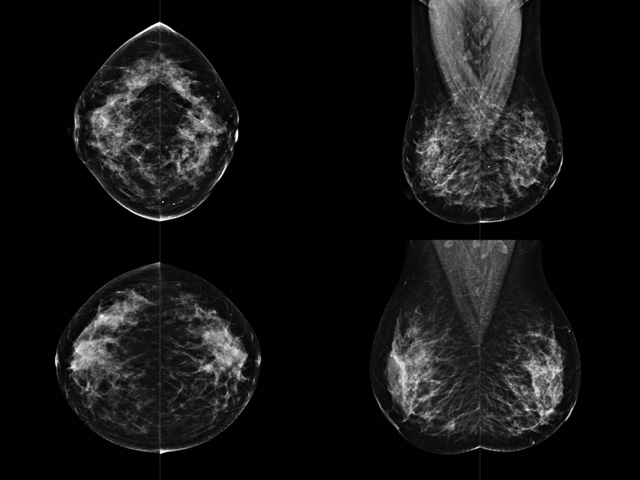

乳腺DR成像設備中非晶硅跟非晶硒兩種平板探測器。更要提供優(yōu)質(zhì)的圖像質(zhì)量乳腺的組織結(jié)構(gòu)與厚度各不相同,減少重拍率輻射劑量,,乳腺的主要構(gòu)成組織均為軟組織結(jié)構(gòu),組織之間密度十分相似,缺乏天然對比度。選擇軟X線攝影技術(shù)獲得良好對比度的乳腺結(jié)構(gòu)影像。增加各組織對X線的吸收差異。乳腺攝影測和分類,平板探測器的像素尺寸范圍應在50到100μm之間。特別是微鈣化灶可以小到100到200μm,平板探測器都必極小微鈣化灶進行成像。

乳腺DR是利用X光來做檢查,在一瞬間將被檢測到的位置投影出來,因為是瞬間的輻射,所以只需要0.5秒的時間。因此對病人的輻射很低,大約是0.023mSv,比國家的標準要低得多。DR系統(tǒng)由 X線、發(fā)生裝置、直接轉(zhuǎn)換平板探測器、系統(tǒng)控制器、影像監(jiān)視器、影像處理工作站等組成。能檢查胸腔積液、肺結(jié)核、大葉性肺炎、肋骨骨折等。心室增大、主動脈擴張、主動脈瘤等心臟病。腹部病變,如腸梗阻、腸穿孔等,DR上可見液氣平面、膈下游離氣腫。DR表現(xiàn)不正常,要結(jié)合臨床表現(xiàn)、體征、癥狀等綜合分析,結(jié)合CT、彩超、血液分析等,才能作出正確的判斷。